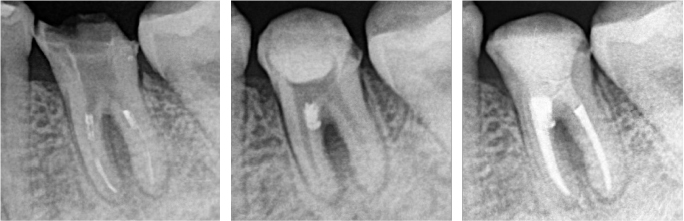

パーフォレーションの確認

本来の根管は上記の赤矢印ですが、パーフォレーションを起こした部位にファイルを挿入すると、根管ではない位置に器具が進みました(黄矢印)。これにより、歯の周囲の骨吸収の原因はこのパーフォレーションであることが確定しました。